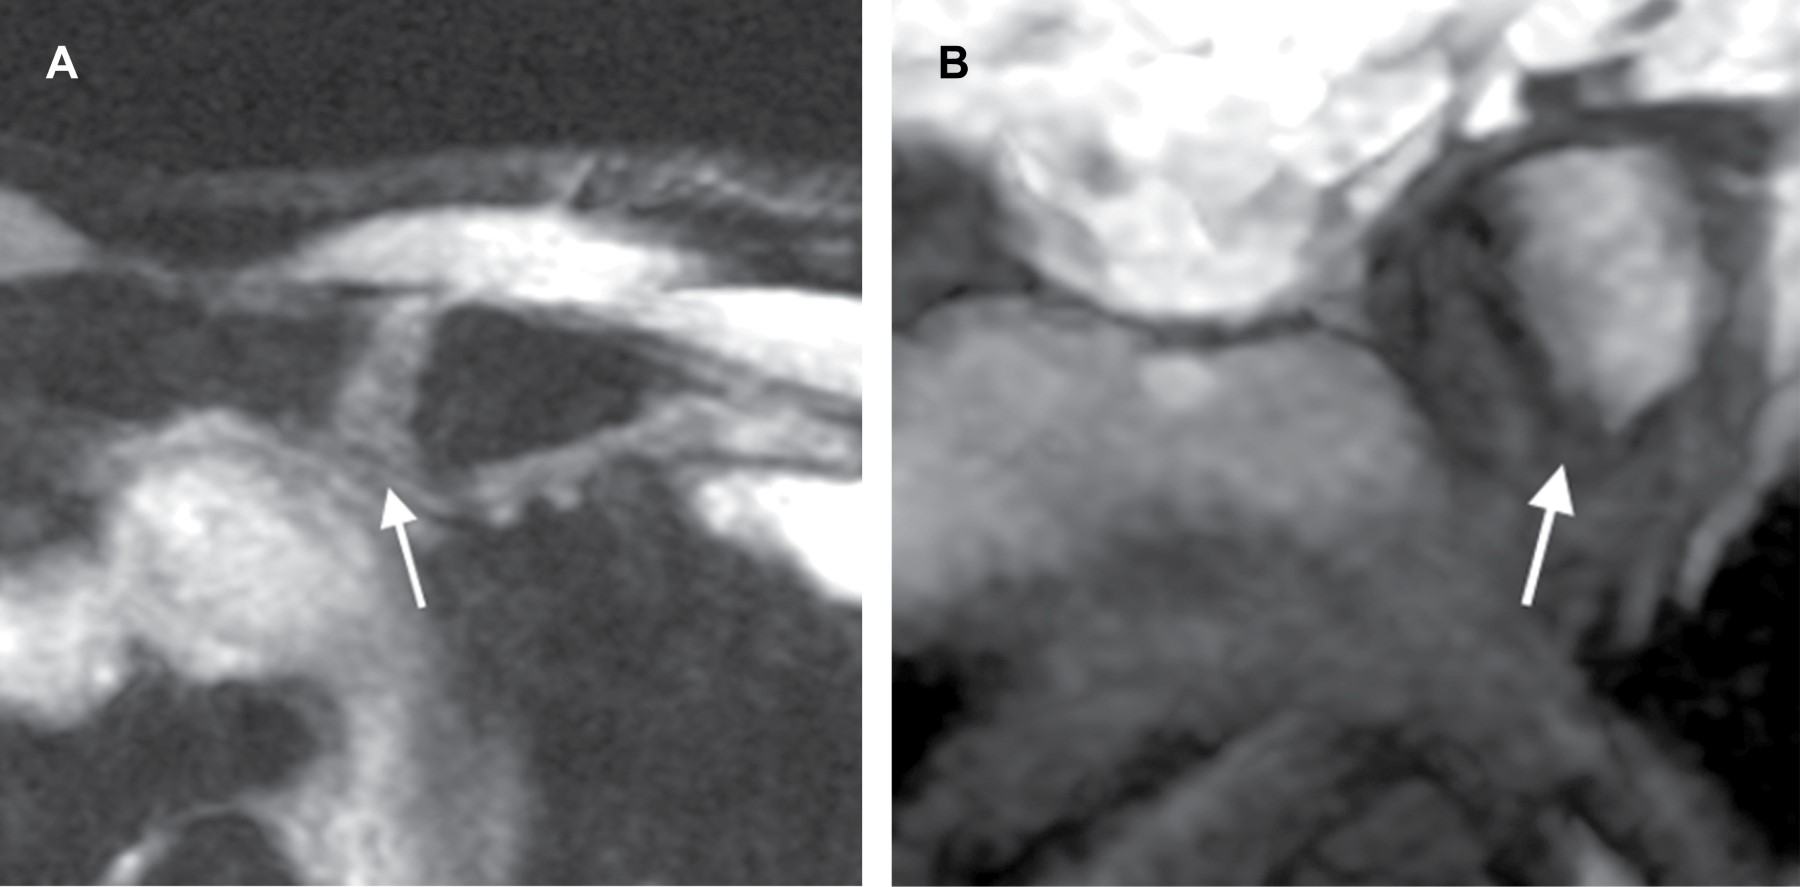

Mujer de 22 años que inicia con dolor focal y aumento de volumen en topografía de la articulación esternoclavicular izquierda de tres semanas de evolución. Negó traumatismos o algún otro factor desencadenante. Su médico le solicitó resonancia magnética, en la cual se aprecia engrosamiento e irregularidad del cartílago articular con predominio en la región inferior-interna de la articulación, asociada a edema subcondral (Figura 1).

Las modalidades por imagen que se utilizan son radiografía convencional, tomografía computarizada, gammagrafía, ultrasonido y resonancia magnética, esta última es excelente para mostrar anomalías cartilaginosas, articulares y óseas.

Los hallazgos característicos por resonancia magnética son engrosamiento del cartílago con aumento en la intensidad de señal de manera focal o generalizada en secuencias T2, STIR o T2 Fat Sat, edema subcondral y reforzamiento tras la administración de medio de contraste (Figura 2).